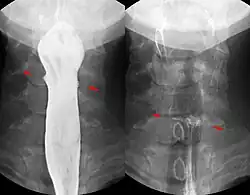

Magnetische Fremdkörper: Wenn magnetische Kleinteile (z. B. aus einem Magnetbaukasten) verschluckt werden, besteht die Gefahr, dass sich diese aufgrund ihrer Anziehung zueinander oder zu einem anderen verschluckten Eisenteil festsetzen. Ein normaler Abtransport ist dann oft nicht möglich. Es kann auch zur Anziehung von zwei Magnetteilen in zwei verschiedenen Darmschlingen kommen, so dass es dazwischen zu einer Druckschädigung des Darmes in kurzer Zeit letztlich mit Darmperforation desselben kommt. Daher wird eine gesondertes Vorgehen bei Verschlucken von mehr als einem magnetischen Fremdkörper empfohlen, was in vielen Fällen auch die operative Entfernung der Magnete einschließt.[3][4]